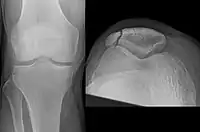

Vertical patella fracture